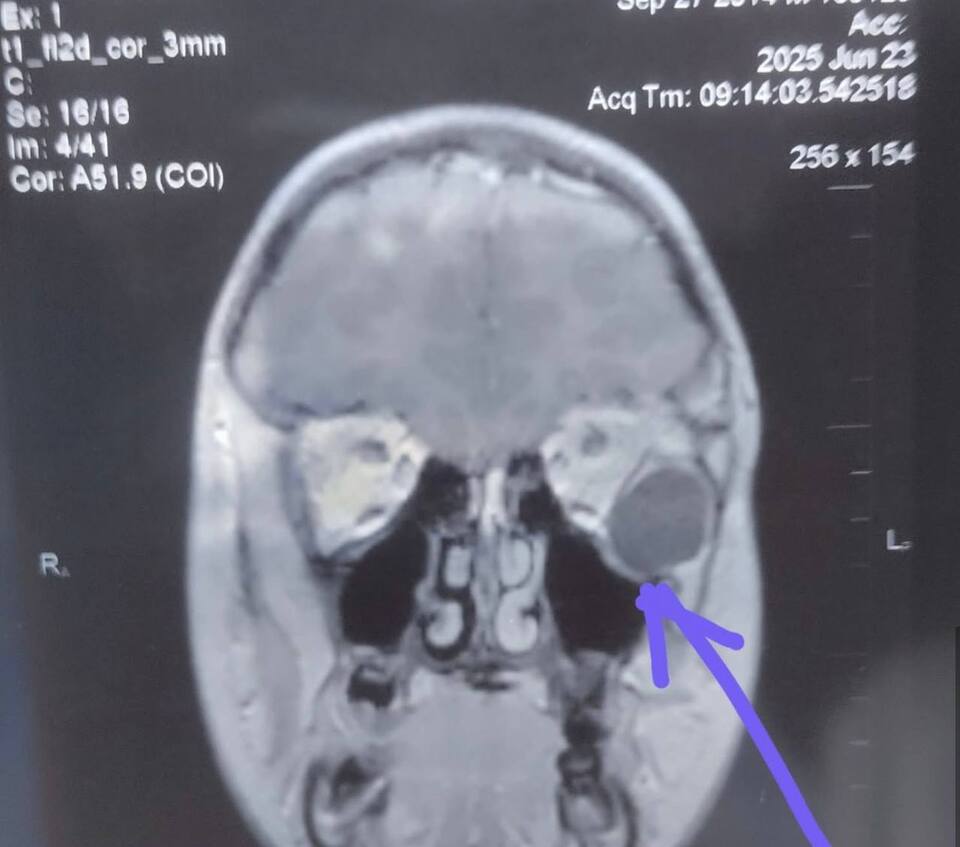

Після проведення МРТ обстеження виявили новоутвір великих розмірів (приблизно 20 мм), який зміщував очне яблуко та викликав у дитини наявні симптоми.

Патогістологічне дослідження підтвердило діагноз — дермоїдна кіста.